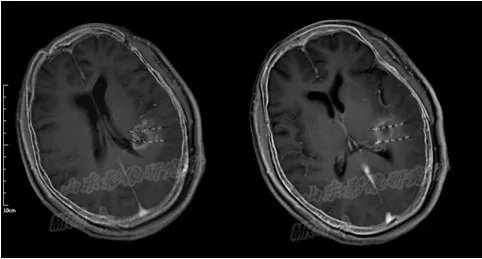

术后24小时内MRI/CT图像融合

MR/CT融合图像解决了I125放射性粒子在磁共振图像上显示不清、CT图像病灶轮廓勾画

困难的缺点,达到精准的病灶与粒子的空间分布显示,有利于术后的TPS验证。